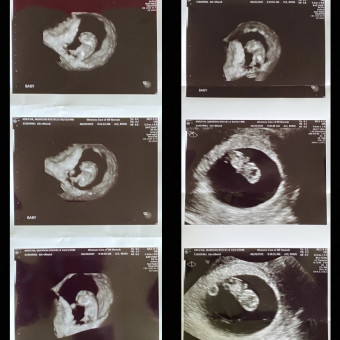

We are so excited to welcome our little bundle of joy come January!